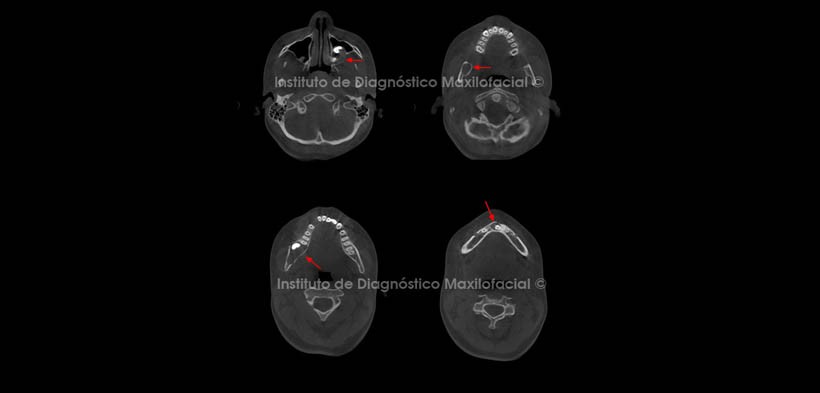

Al estudio tomográfico volumétrico (CBCT) mediante cortes axiales (Fig. 2), reformación panorámica (Fig.3) y reconstrucciones 3D (Fig. 4) apreciamos lesiones isodensas localizadas en el maxilar superior: a nivel de la corona de la pieza 2.8, la misma que se encuentra desplazada cefálicamente.

En el maxilar inferior a nivel coronal de las piezas 3.2 y 4.3, que se encuentra impactada en posición mesioangular, y a nivel del cuerpo y rama mandibular del lado derecho, provocando leve expansión de la tabla ósea lingual y desplazamiento cefálico de la pieza 4.8 así como caudal con aparente impactación de la pieza 4.7.